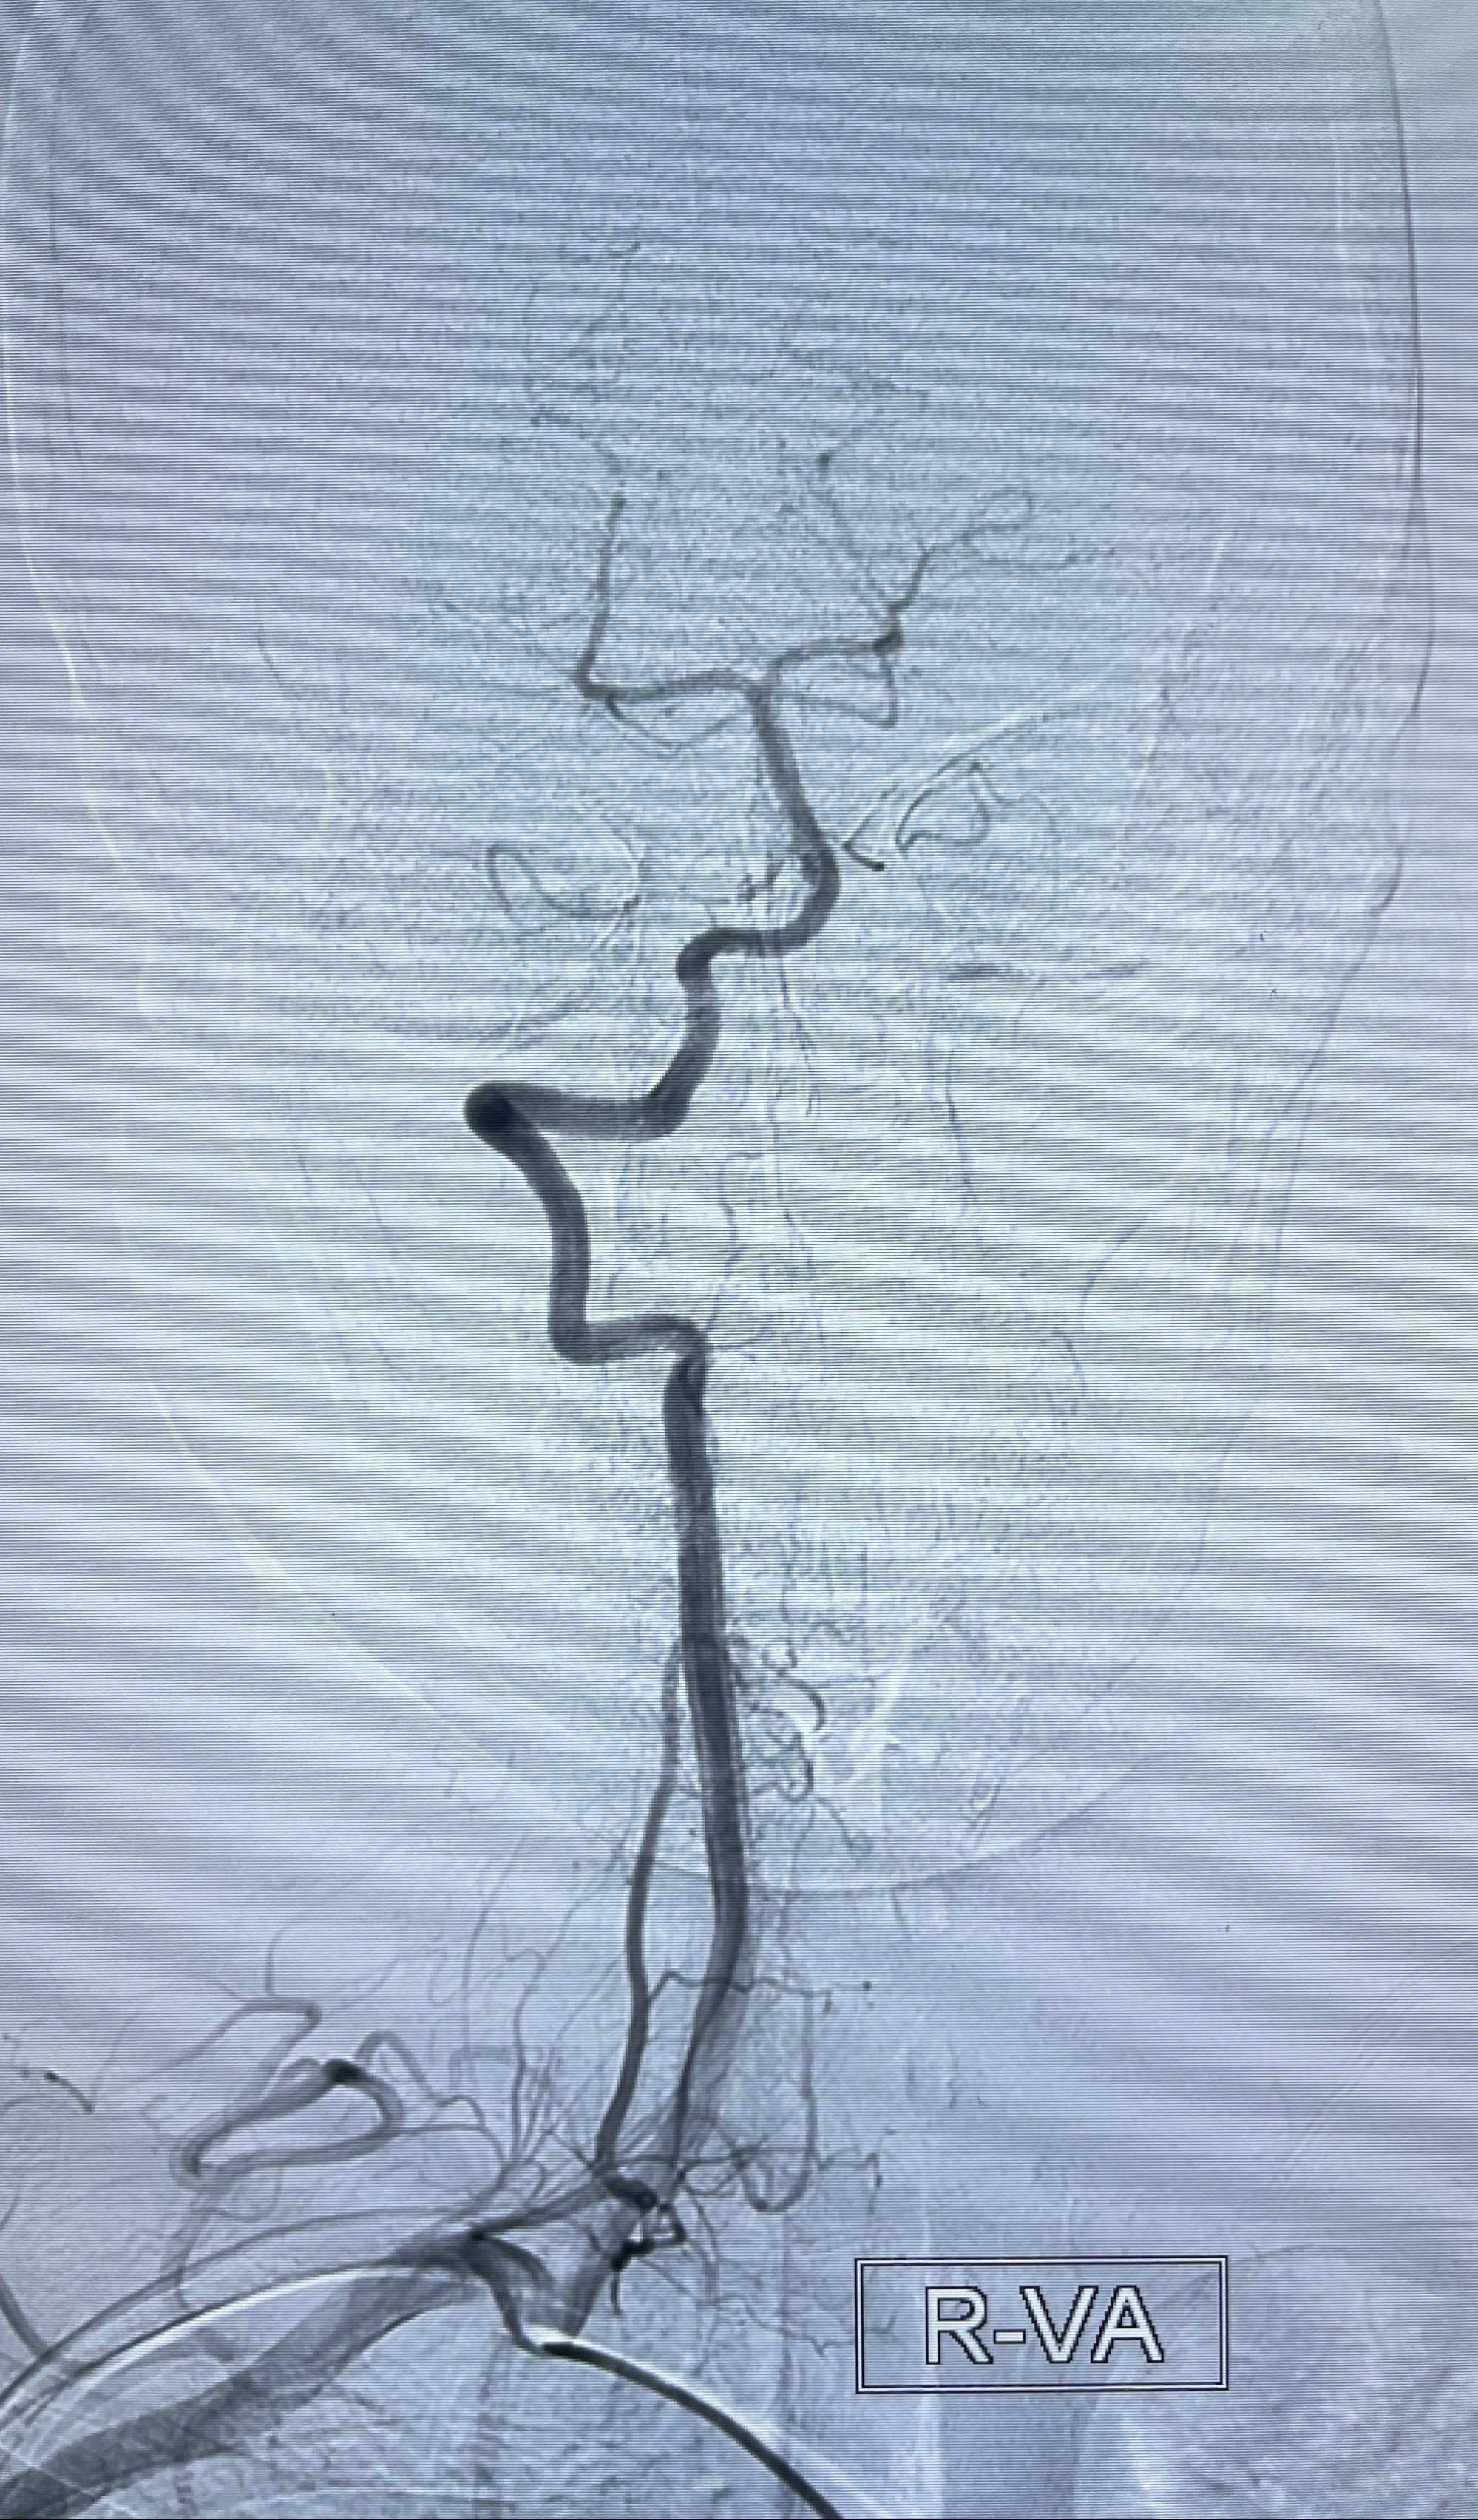

2023-08-14DSA:

左侧大脑中动脉动脉瘤,约2.6-2.8-3.4-2mm大小(瘤颈部、瘤体部、瘤高)